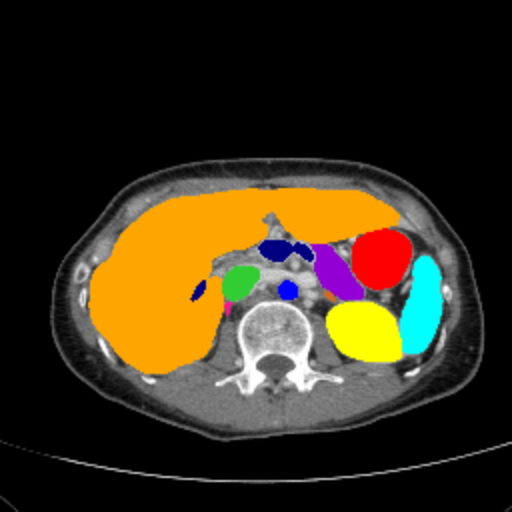

Figure 3 presents a qualitative comparison of segmentation performance on examples from the Synapse, BTCV, ACDC, and ISIC17 datasets. The first two examples (from Synapse) highlight variations in segmentation performance among U-Net, TransUnet, Mamba-Unet, and Swin-Unet. While Swin-Unet performs well in the first example, its performance decreases in the second example, particularly in segmenting the organ highlighted in blue. Additionally, it misclassifies background regions as the class highlighted in orange. In contrast, our approach demonstrates high robustness in segmenting all classes accurately and aligning well with the ground truth masks.

Across BTCV, ACDC, and ISIC17, the comparison methods exhibit varying performance depending on the task and class. For instance, Mamba-Unet struggles to segment multiple organs in BTCV, even misclassifying certain classes as others. In the ACDC dataset, both TransUnet and Mamba-Unet perform poorly in segmenting the three classes. In the last column (ISIC17), Swin-Unet oversegments the skin lesion compared to the ground truth. Unlike the comparison models, our approach consistently delivers effective segmentation across different tasks and datasets.

These qualitative findings further reinforce the quantitative results presented in the experimental section, demonstrating the effectiveness of our MambaCAFU model in handling binary and multi-class segmentation across diverse medical imaging modalities and tasks.

Slice GT Unet TransUnet Mamba-Unet Swin-UMamba MambaCAFU-V1

Figure 3: Visual comparison of segmentation examples from Synapse (first two examples), BTCV (3-4 examples), ACDC (5th example) and ISIC17 (last example). Columns: input slice, ground truth, Unet, TransUnet, Mamba-Unet, Swin-UMamba, and MambaCAFU-V1.